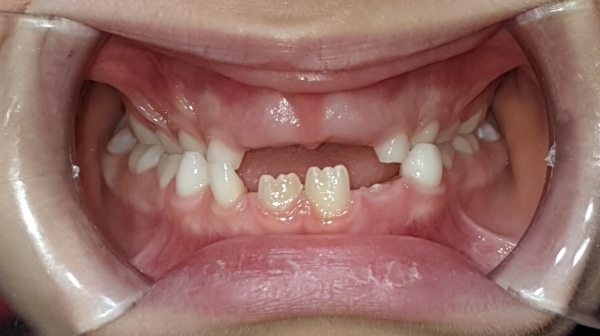

ANTES